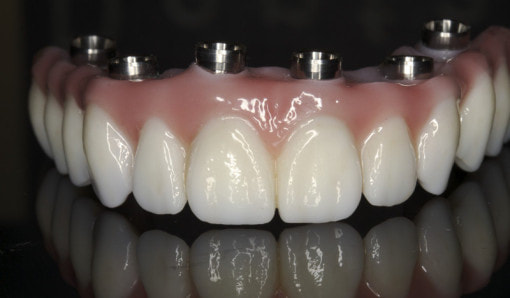

Chip-free, precision milled CAD/CAM Zirconia Oxide Ceramics is the best treatment option for replacing missing teeth. Dr. Andrews is one of few dentists in Greater Boston, who offers this amazing dental technology to his patients. It has no metal, no acrylic, or any other type of resin that often chips or degrades over time. It is made of 100% Zirconia Ceramics in the Certified USA dental laboratory. It comes with DENTOLOGY life-time free warranty.

Full arch Implant Bridge replaces all of your upper and/or lower teeth. They are permanently supported on four or six dental implants. Prettau Zirconia Implant Bridge looks, feels and functions just like healthy, natural teeth. It is amazing what modern dentistry has to offer for all teeth replacement.

After completion of bone integration (healing) The final prosthetic phase had been accomplished with fabrication of the full contour zirconia non-removable (fixed) bridge.